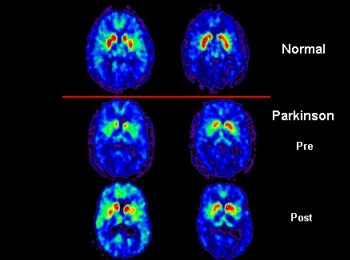

Nerve cells in the brain need a chemical called dopamine to live and be able to control the movement of my muscle. See, you have muscles, too! If the cells that manufacture dopamine in the brain are gradually damaged or destroyed, the brain cannot work properly and the muscles do not get the messages they expect. And nobody knows why the brain cells die off. Dead brain cells cannot make dopamine.